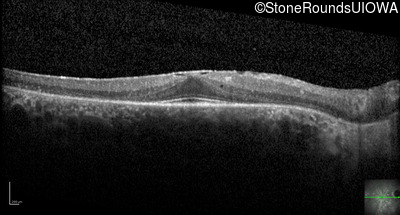

Optical Coherence Tomography - Right - 20/20 -1

Exemplar / OCT Stack

OCT Stack